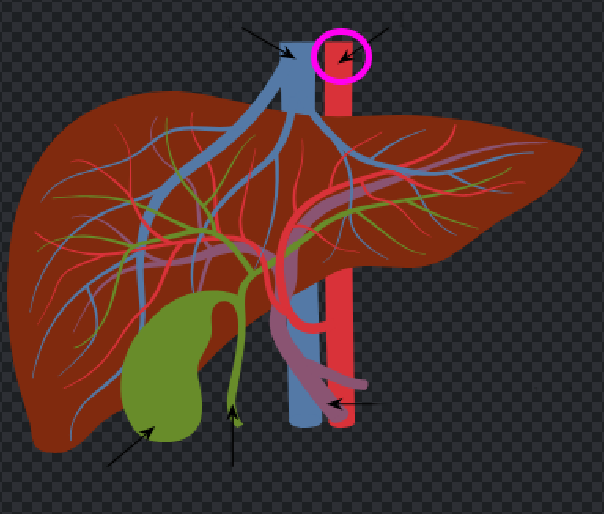

Porta hepatis

Inferior vena cava

Hepatic artery

Hepatic portal vein

Fundus of gallbladder

Cystic duct

Left hepatic ducts

Right hepatic ducts

Common hepatic duct

Common bile duct